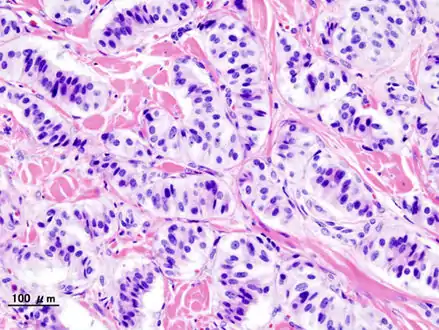

| Pathology of pancreatic endocrine tumour (insulinoma). | |

Pancreatic insulinoma